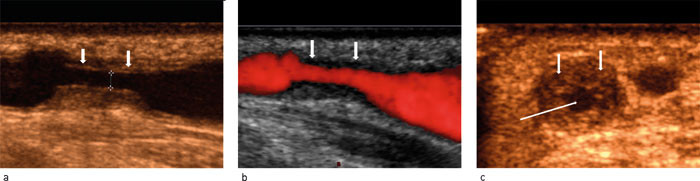

I de siste ti årene har utviklingen innenfor ultralydteknologien medført høy bildekvalitet og oppløselighet. Armens blodkar ligger godt tilgjengelig for undersøkelse med ultralyd, som er en ikke-invasiv metode, skånsom for pasienten, og utføres uten bruk av kontrastmiddel (fig 1). Med tillegg av dopplerteknikk kan også hemodynamiske forhold evalueres. En rekke studier har vist høy treffsikkerhet for ultralyddoppler i diagnostikken av stenoser (14) – (18). Som rutine ved ultralydundersøkelse inngår også måling av blodstrøm (blodvolum per tidsenhet) i fistelen, hvilket samsvarer godt med blodstrømsmålinger under dialyse, og har en viktig prediktiv verdi for dysfunksjon av en fistel (2, 9, 19, 20).

Høy blodstrøm kan føre til utvikling av veggforandringer i venen (intimahyperplasi) som gradvis kan forårsake innsnevring av venen, og ev. en signifikant stenose. Med ultralyddoppler kan en stenose lokaliseres og graderes basert på doppler- og diametermålinger, og blodstrøm i fistelen kan måles og sammenliknes med tidligere verdier (fig 2). Ved påvist signifikant stenose, ofte kombinert med målt synkende blodstrøm i fistelen, foreligger vanligvis indikasjon for snarlig PTA-behandling (fig 3) (4, 9, 27).